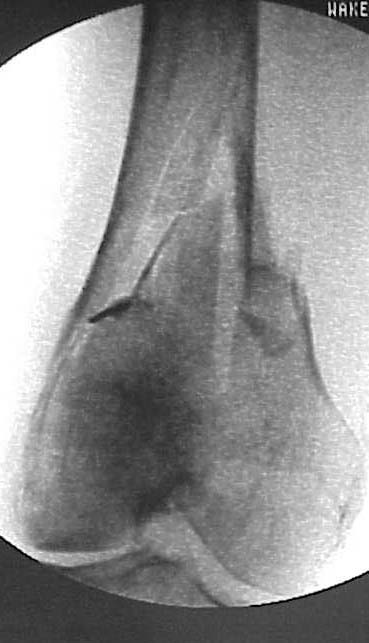

This patient generated much discussion at our institution whether a retro IMN, blade plate or LISS would be appropriate. The notch is 17 cm from the tip of the THA and I felt that the stress riser could be a problem and would feel terrible if she broke b/t the implants. The THA is so large that a blade or LISS would be difficult to get proximal purchase.

As Chip pointed out the injury was 4-7-01. No miracle, Chip, but her fixation w/ a LISS appears stable at 6 weeks w/ 0-90 knee motion. The proximal fixation is unicortical posterior to the prosthesis. Hope she continues to consolidate.

This looks good on present films - but some theoretical concerns.

Proximal femoral component support seems to be fading (stress shielding vs osteolysis) but it looks solid distally.

Doesn't the introduction of proximal plate screws set up the possibility of crevice and galvanic corrosion at a point in the femoral stem that is already at risk for cantilever mode failure?

If that is an issue and one removes LISS hardware after fx healing, what about stress risers through screw holes in the vicinity of the tip of the prosthesis?

It looks as if there are a few extra drill holes. Is that because of poor purchase in osteoporotic bone or a technical issue with the LISS procedure? I believe it can be difficult to get good fixation of a standard DHS sideplate even under direct vision in some osteoporotic femurs.